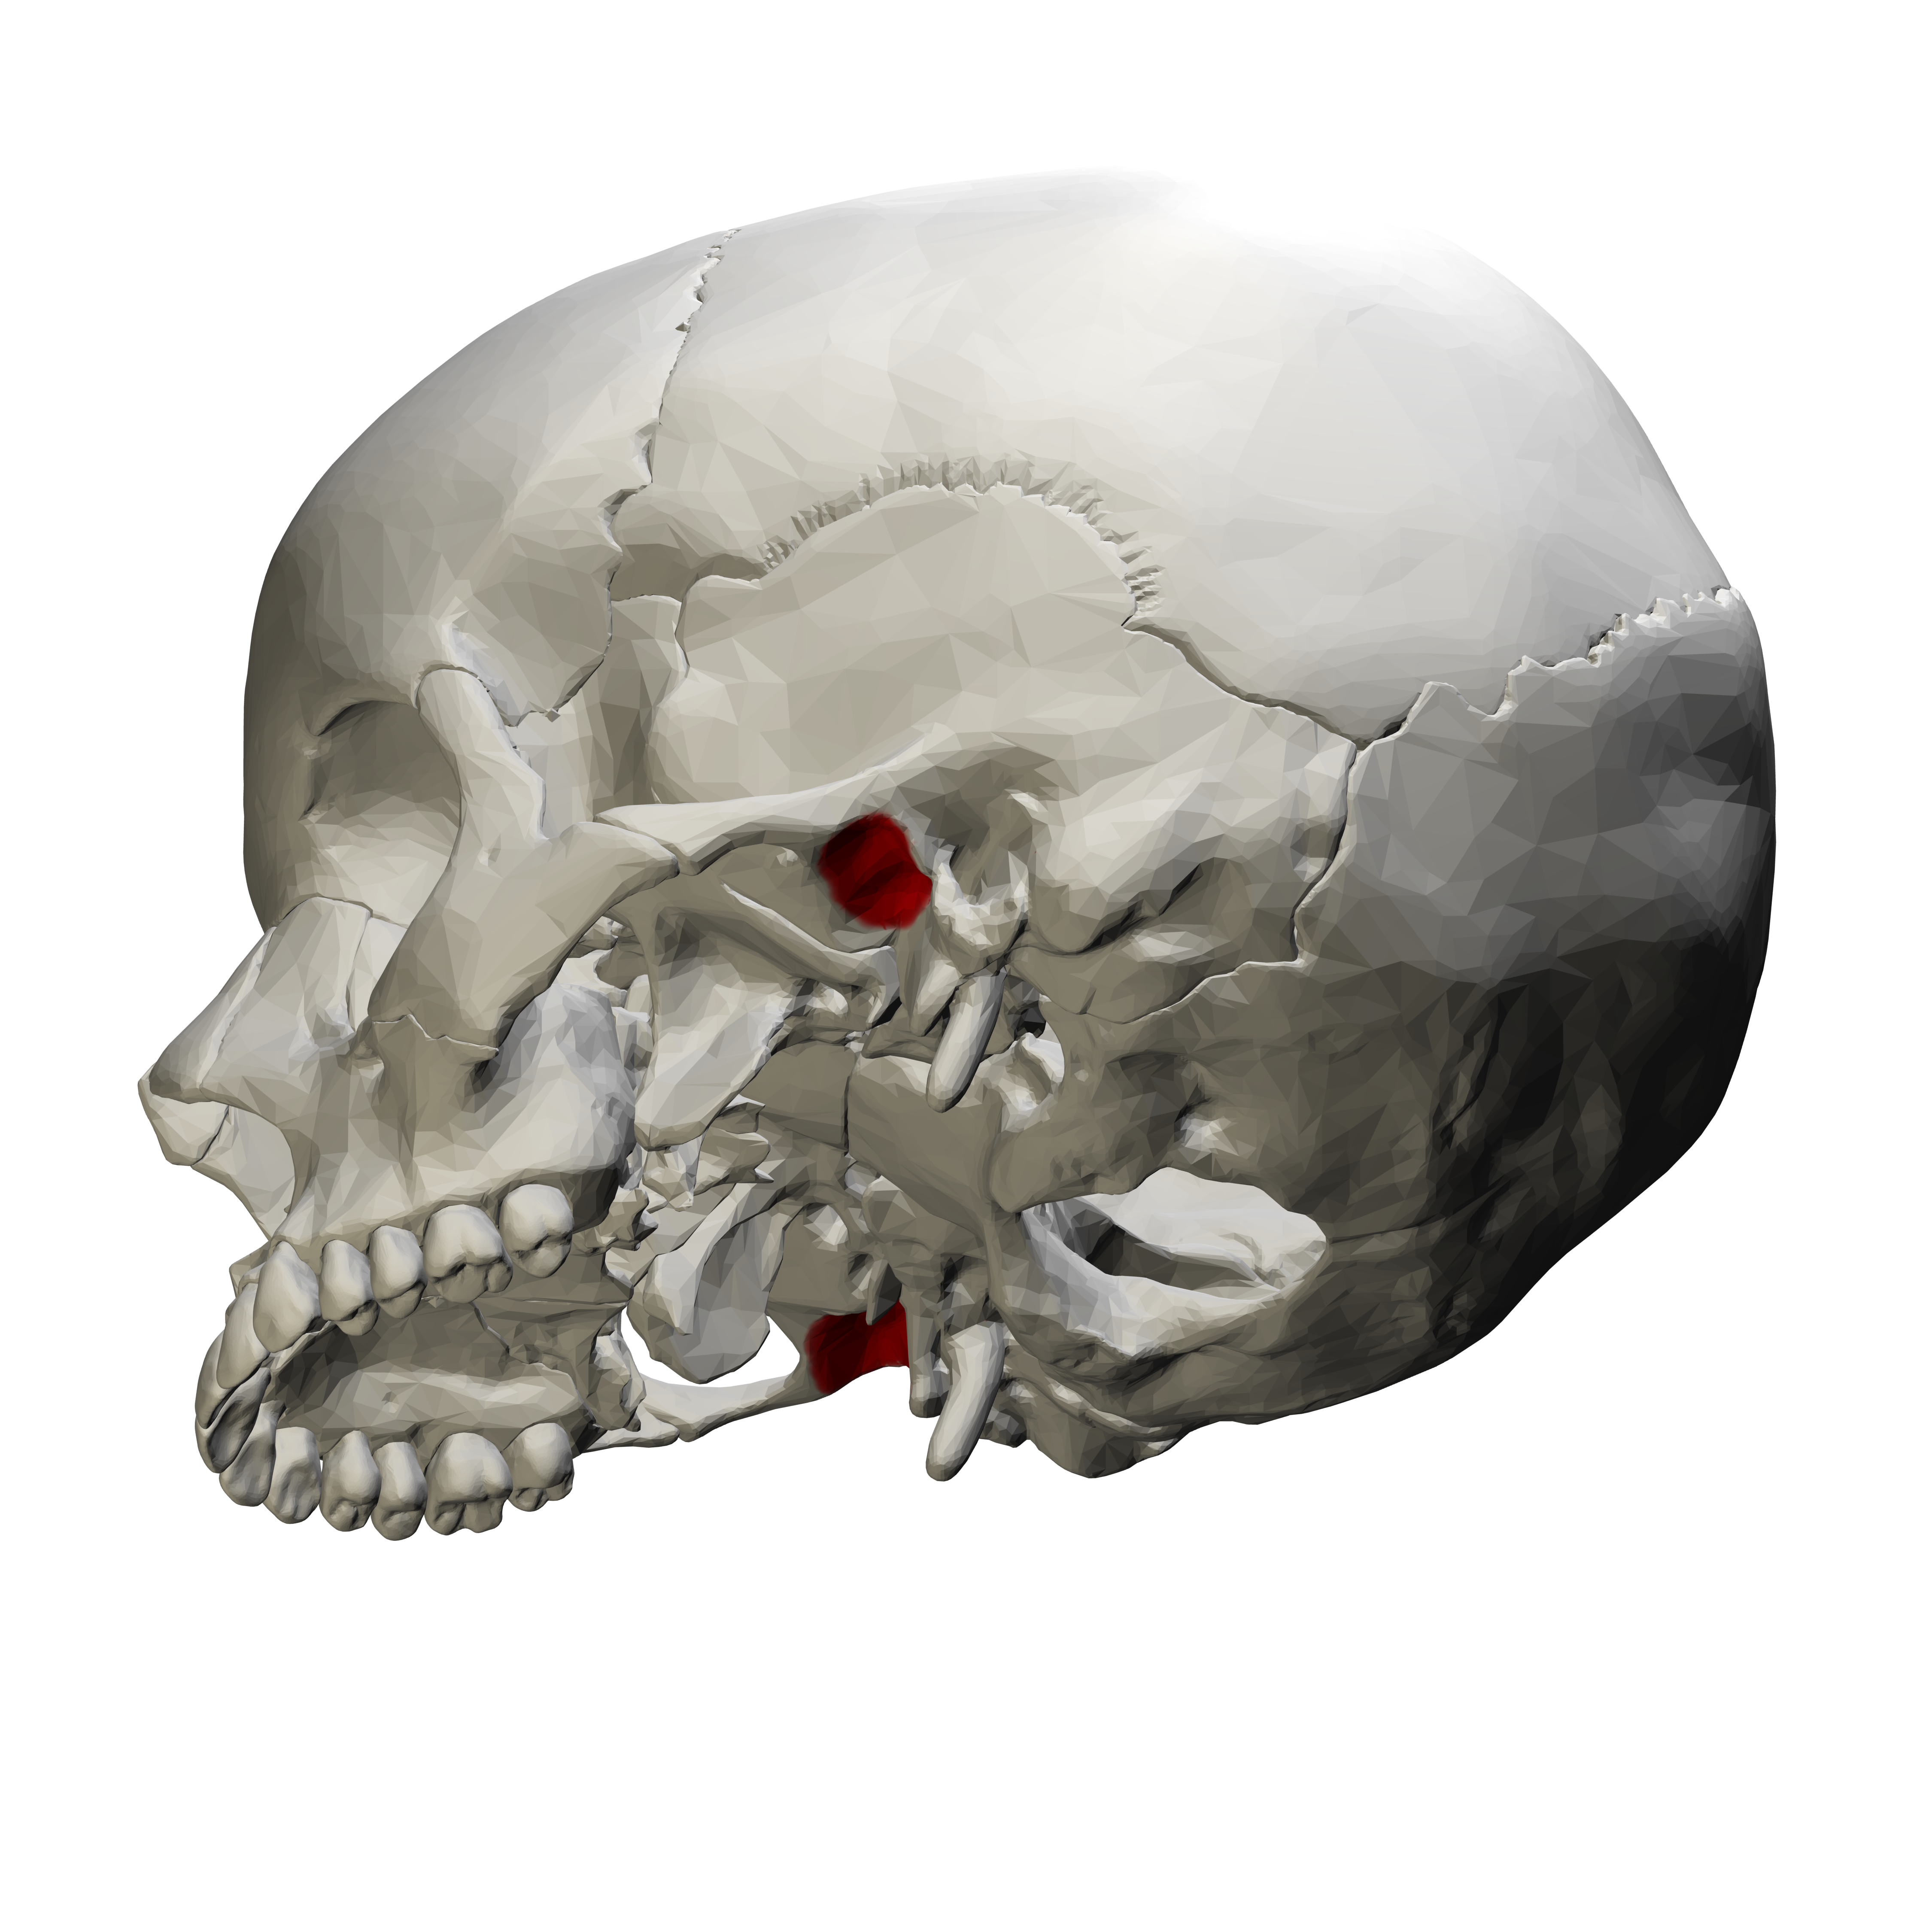

lateral pterygoid plate

thin, wing shaped extension of sphenoid located distal to maxillary tuberosity region

rounded radiopaque projection, not seen intraorally

pterygomaxillary fissure

narrow space that separates the lateral pterygoid plate and maxilla

rounded radiolucent area. not seen intraorally